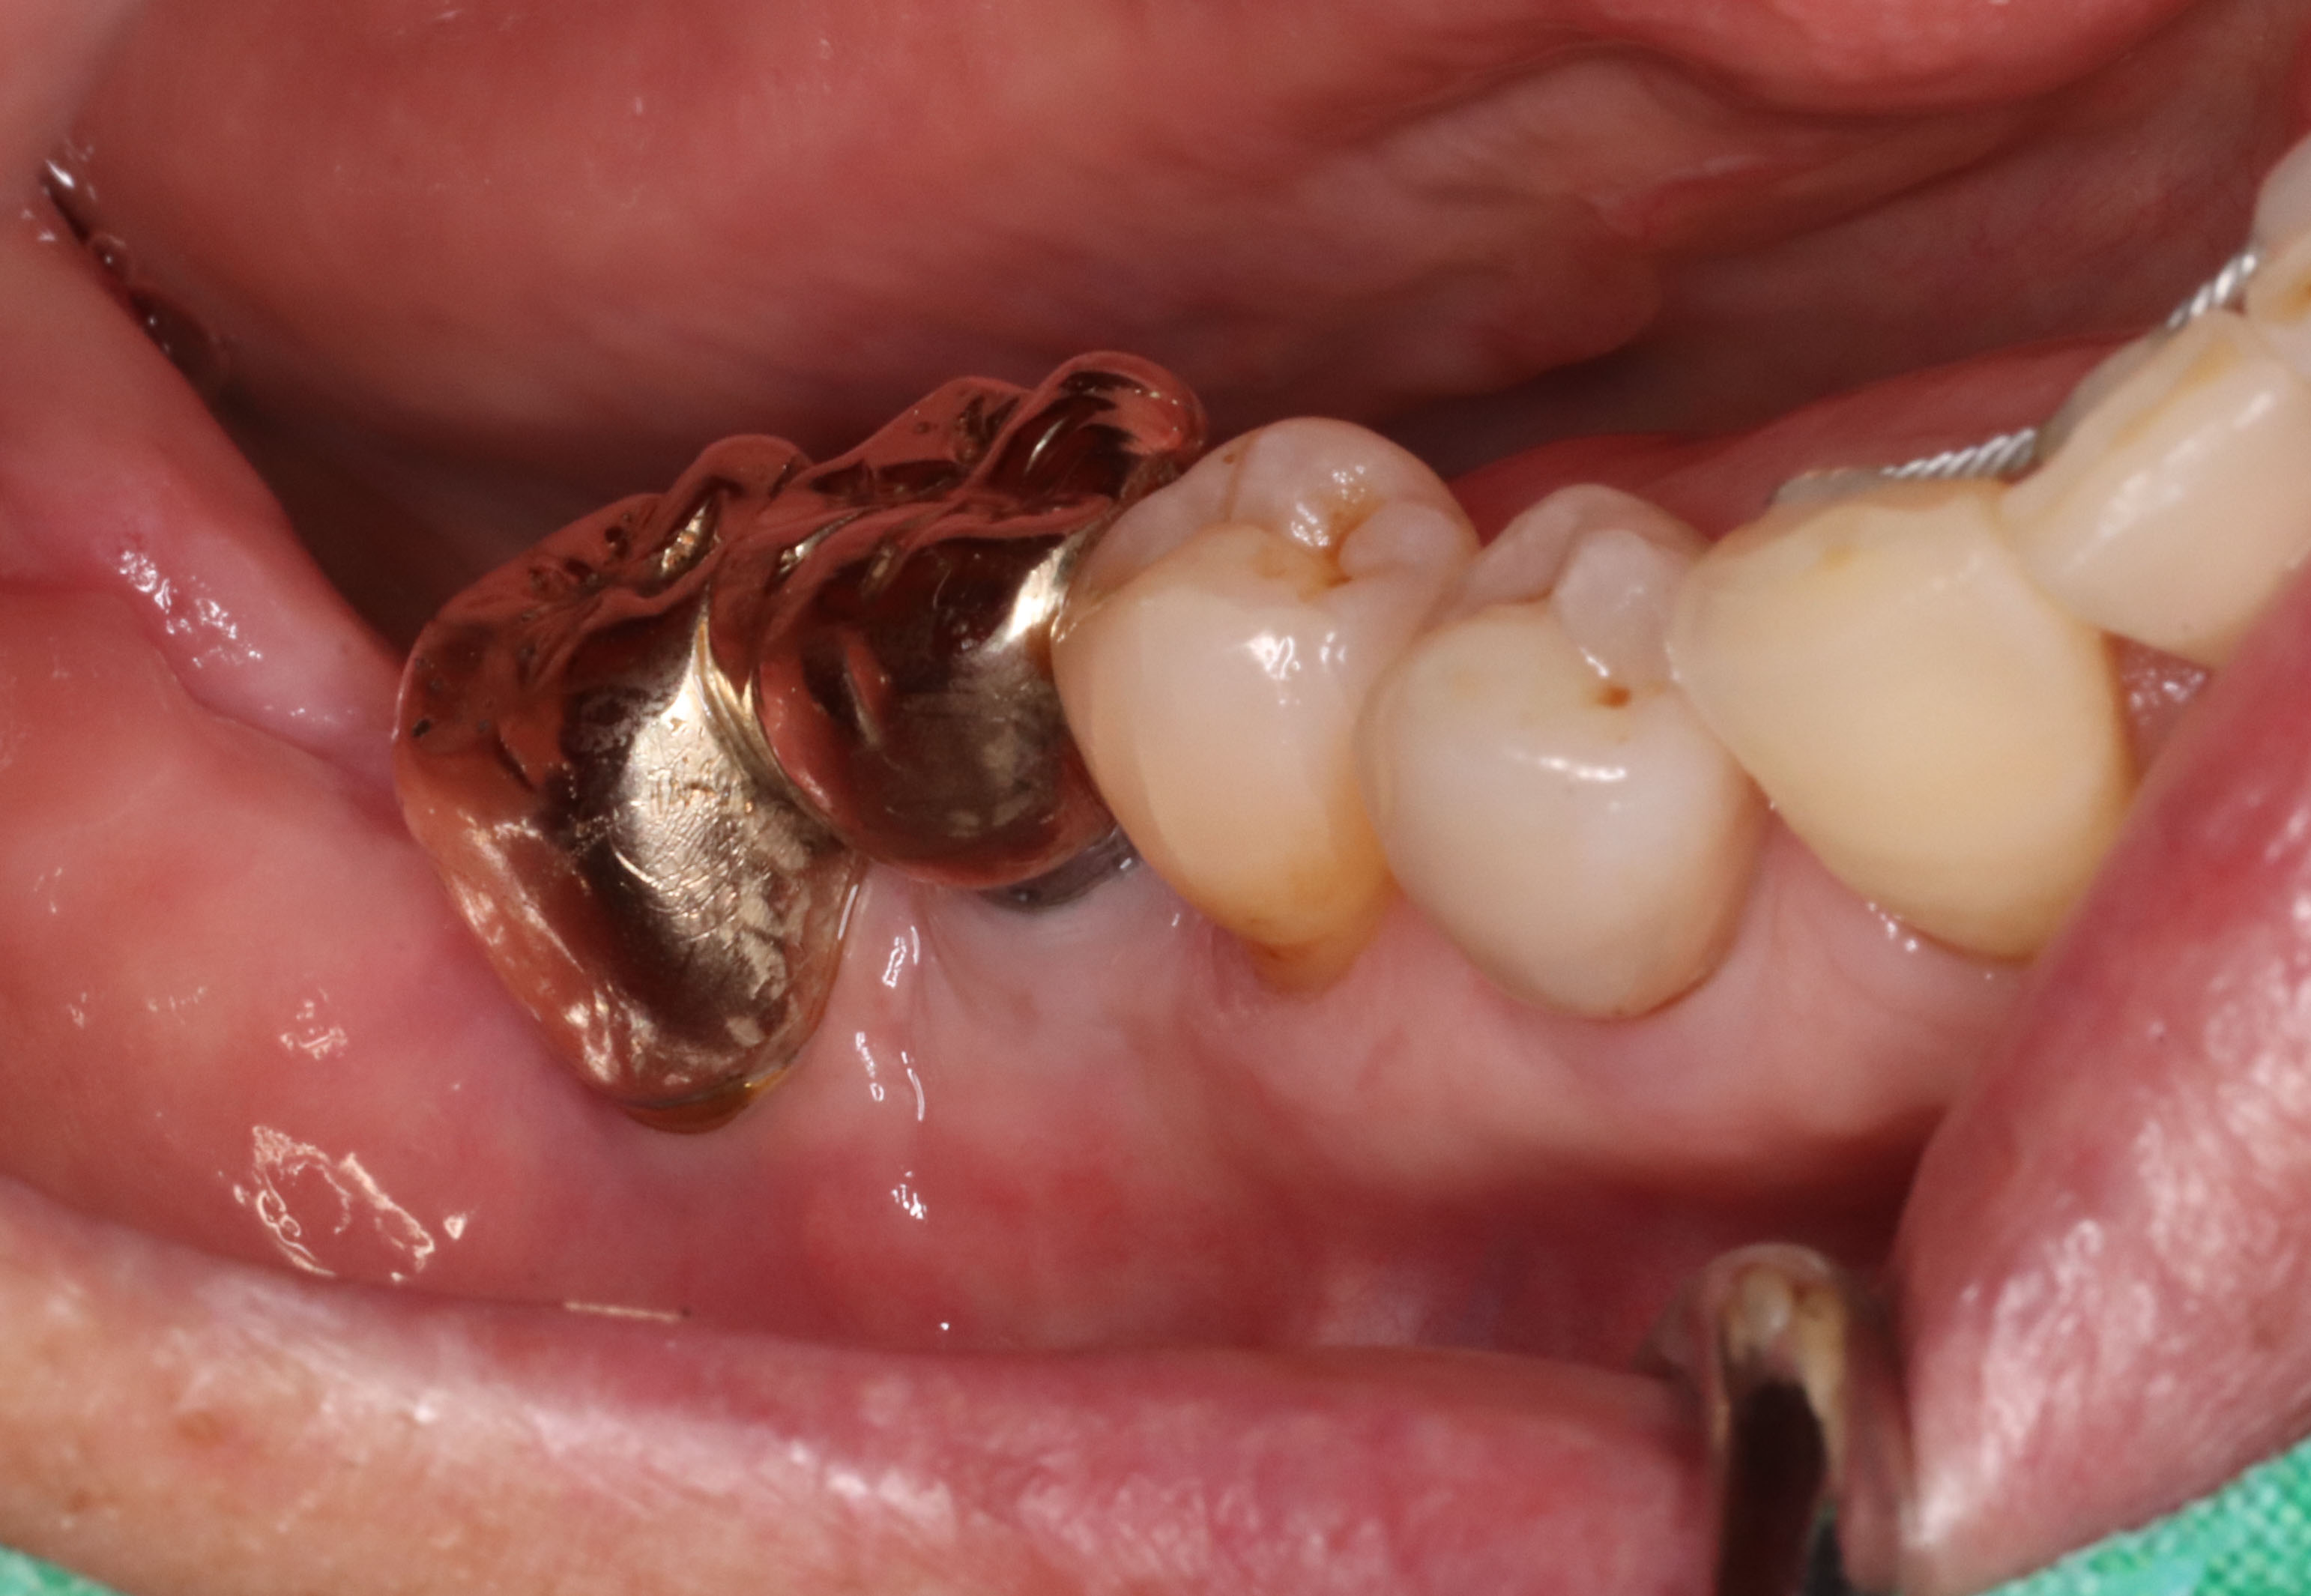

Here is the current state of implant placement after the procedure.

This is a photo from 2004.

This is from 2008

This is from 2011

This is from 2021

It's 2021 too.

These days, although not commonly used, it seems that external hex type implants have advantages when creating multiple screw-type prosthetics.